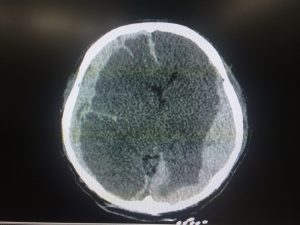

A traumatic brain injury happens when the delicate neurological tissues of the brain are injured within the skull. The skull bone does not have to break for the brain to be injured. Brain injuries can vary in severity from a minor concussion to a life-threatening, catastrophic injury. The neurological tissue in the brain does not heal and regenerate as easily as does bone, muscle, and tendon. In many cases, brain damage is permanent.

During an accident, the motorcyclist is traveling at speed and comes to an abrupt halt, often when striking the pavement. When the head hits the pavement, the brain strikes the bony skull and then bounces in the fluid that surrounds the brain. This can cause micro-tears in the blood vessels that feed the brain and lead to a blood clot. It can also cause a shear injury, during which the long connecting nerves of the brain are torn. This is also called a diffuse axonal injury.

- Hematoma: This is blood that builds up in the brain after an accident. It increases pressure inside the skull. When it’s left untreated, it can lead to a loss of consciousness, permanent brain damage, or death. When the blood builds up on the surface of the brain, it’s called a subdural hematoma. This requires immediate emergency treatment. Symptoms may develop immediately or can develop over several weeks.